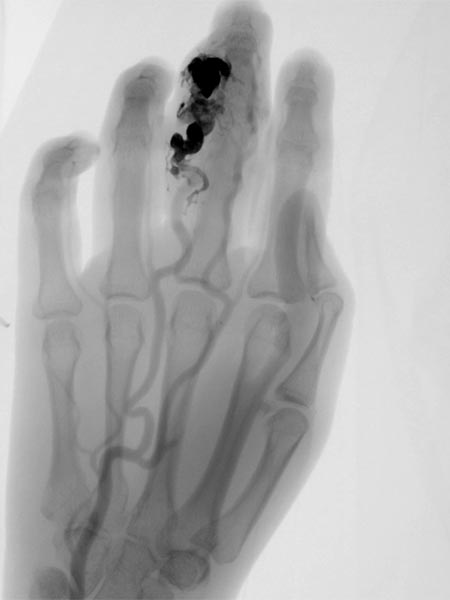

26-jährige Patientin mit Rezidiv einer AVM am Digitus III der rechten Hand. Ansicht von dorsal und palmar nach erfolgter transarterieller Embolisation vor 2 Jahren. Rezidivierende, schmerzhafte Schwellung D III mit tastbaren Pulsationen und Schwirren.

Nach bereits erfolgter transarterieller Teilembolisation der AVM am Finger vor 2 Jahren zeigt sich ein Rezidiv der AVM. Bei der Embolisation wurde nur ein Teil der AVM verschlossen, dies erhöht die Gefahr eines Rezidivs. Der alte Cast der vorherigen Embolisation ist zentral als Kontrastmittelaussparung zu erkennen.

Das Rezidiv der AVM hier in der vergrößerten Zielaufnahme des D III während der Angiographie mit deutlicher Vergrößerung im Vergleich zu den alten Angiographien (nicht abgebildet). Die DSA-Aufnahmen nach transarterieller antegrader Punktion der Arteria brachialis zeigen eine hypervaskularisierte AVM von Fingermittel und -endglied.

Angiographische Abschlußkontrolle mittels Katheterangiographie der rechten Hand von transarteriell über die Arteria ulnaris. Komplette Devaskularisation des AVM Nidus, keine Fast-flow-Shunts mehr angiographisch abzugrenzen. Der Befund ist damit resektionsfähig.

Fluoroskopische Darstellung des Cast nach erfolgreicher Nidusembolisation der AVM. Zur besseren Orientierung für die Operationsplanung erfolgt diese Darstellung auch noch einmal ohne Subtraktion mit sichtbaren Knochen.